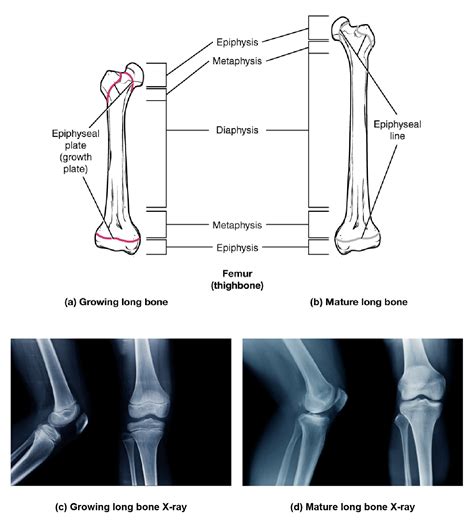

So, what exactly is the proximal epiphysis ? To break it down, let’s start with the word “epiphysis.” The epiphysis is the end part of a long bone. Think of your femur (thigh bone) or your humerus (upper arm bone). Each of these long bones has two ends – the epiphyses. Now, “proximal” simply means closer to the center of the body. Therefore, the proximal epiphysis is the end of the long bone that’s nearer to the torso. For example, the proximal epiphysis of the femur is the end that connects to your hip. This area is super important because it’s where a lot of the bone growth happens, particularly during childhood and adolescence.

The proximal epiphysis contains a special region called the epiphyseal plate, also known as the growth plate. This is a layer of cartilage located between the epiphysis and the metaphysis (the wider part of the bone shaft). Cartilage is a flexible tissue that’s not as hard as bone. The growth plate is responsible for increasing the length of the bone. It’s like a construction zone where new bone tissue is constantly being created. Within the epiphyseal plate, specialized cells called chondrocytes are hard at work. These chondrocytes multiply and produce a matrix of cartilage. As new cartilage is formed, the older cartilage cells become calcified, meaning they harden as minerals are deposited. This calcified cartilage is then replaced by bone tissue through a process called ossification. Ossification is the process of bone formation, where osteoblasts (bone-building cells) lay down new bone matrix on the calcified cartilage. This continuous cycle of cartilage production, calcification, and ossification leads to the lengthening of the bone. The growth plate remains active until the end of puberty, at which point hormonal changes cause it to gradually close. Once the growth plate is completely ossified, bone growth stops, and the epiphysis fuses with the metaphysis.

The epiphyseal plate is organized into distinct zones, each with a specific function. These zones include the resting zone, proliferative zone, hypertrophic zone, and ossification zone. The resting zone is closest to the epiphysis and serves as a reservoir of chondrocytes. The proliferative zone is where chondrocytes actively divide and multiply, increasing the number of cells. The hypertrophic zone is characterized by chondrocytes that enlarge and mature. These cells produce enzymes that promote the calcification of the cartilage matrix. Finally, the ossification zone is where new bone tissue is formed. Osteoblasts invade the calcified cartilage and deposit bone matrix, replacing the cartilage with bone. This continuous cycle of cartilage production, calcification, and ossification leads to the lengthening of the bone. As new bone is added to the metaphysis, the epiphysis is pushed further away from the center of the bone, resulting in increased bone length.